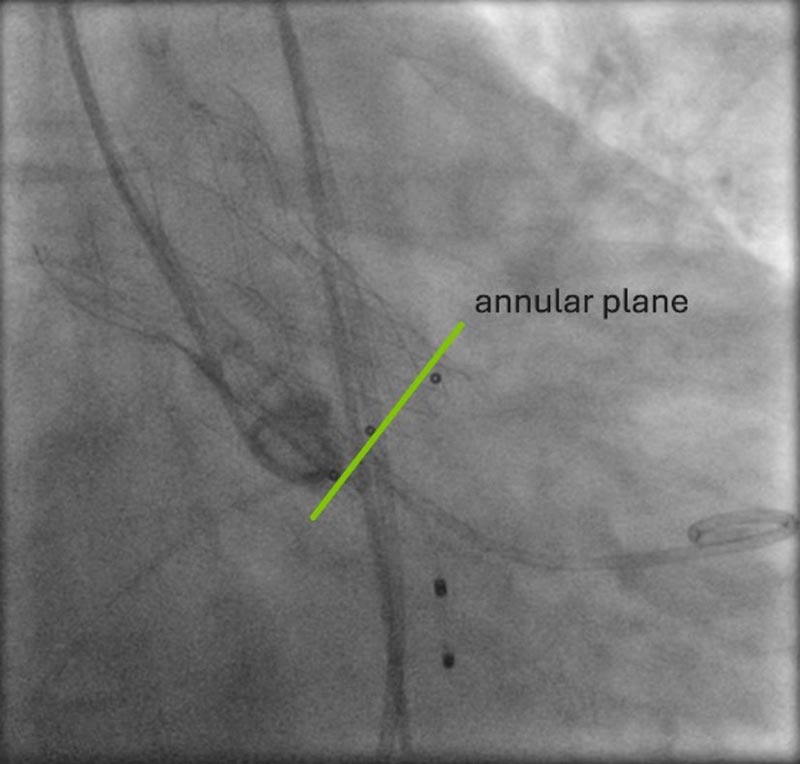

Anschließend wurde das korrekte Crimpen der Navitor Vision 25 mm unter Durchleuchtung überprüft. In einer C-Bogen-Angulation mit Exposition des LCA Ostiums (LCA-view: LAO 31 CRA 10) erfolgte eine Prädilatation der nativen Aortenklappe mit einem 20 mm semi-compliant Ballon (VACS III) unter ventrikulärer Schrittmacherstimulation (180-200/min). Während der vollständigen Balloninflation erfolgte eine Aortographie, die eine ausreichende Distanz zwischen der linken Taschenklappe und dem LCA Ostium zeigte. Die Länge der linkskoronaren Tasche erscheint kürzer als der Abstand des Anulus zur Koronararterie (Abbildung 8, Video 1).

Nach Entfernung der 14F-Schleuse wird die Navitor-Prothese schleusenlos und der Einführungskatheter über die AFC re eingeführt, der flush-port wird auf 12 Uhr orientiert. Die Passage des Aortenbogens und der Aortenklappe waren unkompliziert. Beginnend in der Cusp-Overlap-Projektion(LAO 13 CAU 36) wurde die Klappe langsam und kontrolliert unter wiederholten Injektionen geringer Kontrastmittelmengen über den non-koronar platzierten Pigtail-Katheter implantiert (Video 2).

Obwohl eine extrem horizontale Aorta vorlag, war die Implantation der selbstexpandierenden intra-annulären Klappe unkompliziert, ohne dass es eine Repositionierung / Re-Sheating erforderlich war. Eine bewusst langsame Prothesenfreisetzung hilft, die Klappe positionsstabil bis zur vollständigen Expansion zu implantieren

Die Verwendung der "S-Kurve" der Annulusebene zur Identifizierung von Projektionen, die orthogonal zum Ostium der Koronararterien verlaufen, ist bei der Beurteilung des intraprozeduralen Risikos einer Koronarobstruktion hilfreich, da so die Ausdehnung der Taschenklappen während der Valvuloplastie und der simultanen Aortographie dargestellt werden können.

Dr. Gonska und ihr Team führten den Eingriff entsprechend bestens klinischer Empfehlungen durch und fokussierten die spezifischen Herausforderungen: Um das Risiko einer Koronarobstruktion zu beurteilen, wurde eine Valvuloplastie mit gleichzeitiger Aortenwurzelangiographie in einer anhand der CT bestimmten C-Bogen-Angulation durchgeführt, um das LCA Osmium optimal zu darzustellen (LCA-Projektion). Die Navitor Prothese wurde in cusp-overlap-Projektion implantiert, um eine optimale Implantationstiefe im Bereich des non-koronaren Sinus zu erreichen und damit das Risiko von Leitungsstörungen zu minimieren. Durch bewusst langsames Freisetzen konnte eine stabile Position der Katheterklappe bis zur vollständigen Implantation erzielt werden. Ein paravalvuläres Leck (PVL) wurde erfolgreich durch Dilatation der Aortenklappenprothese behandelt, wobei aufgrund aufgrund der Annulusverkalkungen zunächst ein 20 mm und in der Folge ein 22 mm)´gewählt wurde. Final bestand ein geringgradiges PVL, invasiver Ausschluss eines Gradienten über die Aortenklappenprothese.

Die Fallpräsentation unterstreicht die Bedeutung einer dezidierten CT-Analyse zur Identifizierung spezifischer anatomischer Besonderheiten und zur Bestimmung der C-Bogen-Angulationen für eine optimale Visualisierung der prozedurrelevanten Strukturen. Neben der, insbesondere für die Implantation von selbstexpandierenden Transkatheterklappen etablierten cusp-overlap-Projektion, wurde in diesem Fall eine LCA-Projektion verwendet, um die räumliche Nähe zwischen nativem linkskoronaren Aortenklappensegel und dem LCA Ostium während der Valvuloplastie, die unter simultaner Aortenwurzelangiographie durchgeführt wurde, zu beurteilen.